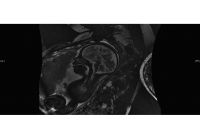

Agenesis of the Corpus Collosum (ACC)

ACC MRI coronal

The corpus callosum is a collection of nerve fibers that connect the two sides of the brain. In agenesis of the corpus callosum (ACC), these nerve fibers are partially missing or completely absent. ACC occurs in approximately in 3 to 7 in 1,000 live births.

ACC axial non-visualized corpus callosum